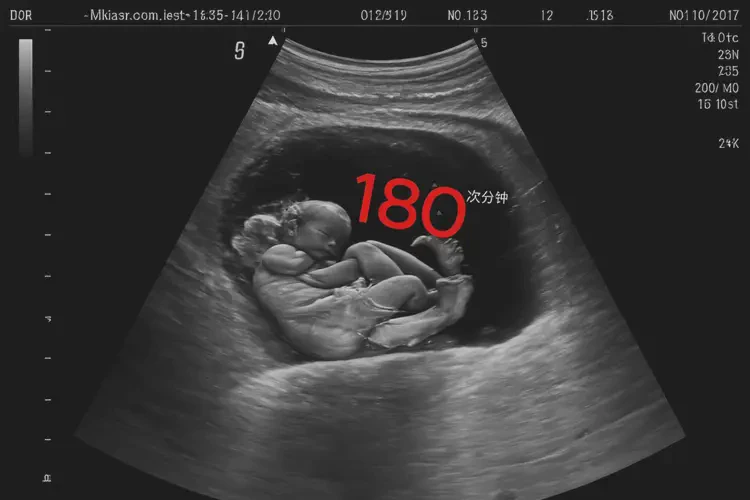

胎心率180次/分钟在孕10周1天属于正常范围,宝宝可以要。

孕10周1天时,胎儿的胎心率在170-190次/分钟之间都被认为是正常的。胎心率会随着孕周的增加而逐渐下降,到孕晚期会稳定在120-160次/分钟。180次/分钟的胎心率在这个时期是可以接受的,并不意味着宝宝有问题。